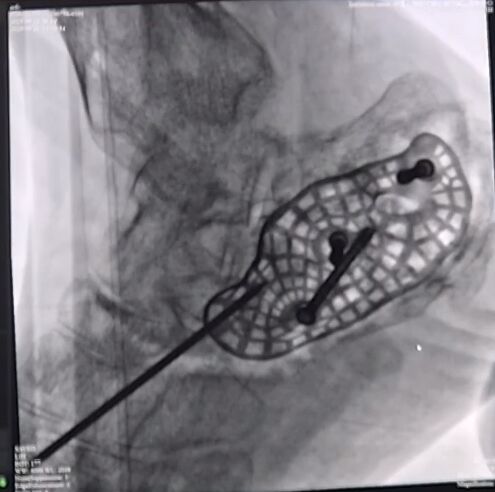

螺钉固定后